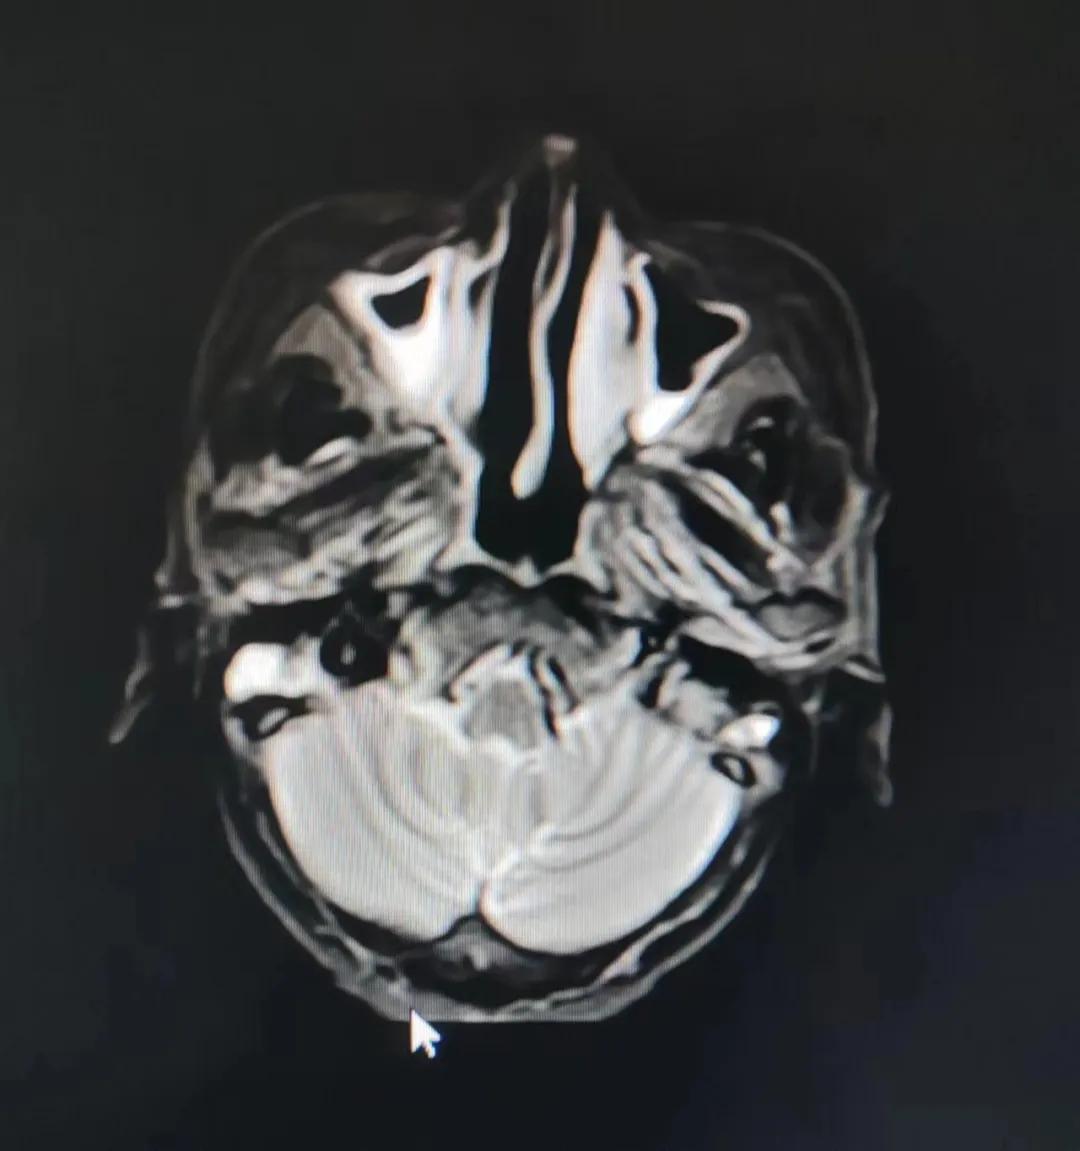

治療后

放療結束,除了放療處的皮膚輕微放射性皮炎外,基本沒有什么不良反應。復查發(fā)現,鼻腔淋巴瘤已不可見,目前患者已康復出院。